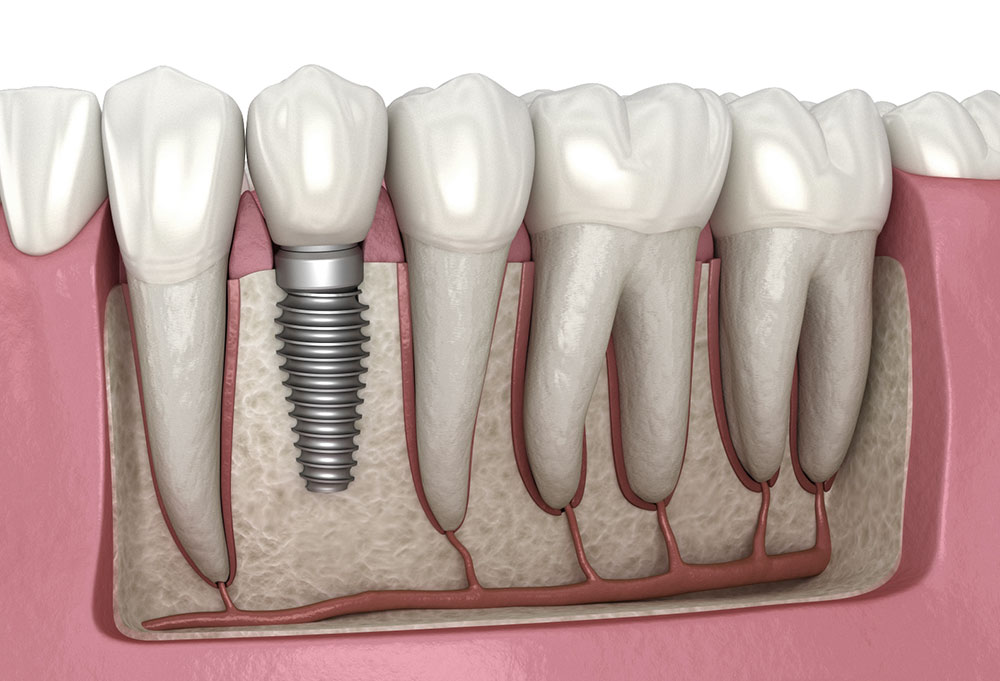

Dental Implants

Missing teeth can affect your ability to chew, speak, and smile with confidence. Our dental implants are designed to look, feel, and function like natural teeth, providing a permanent solution for tooth loss.